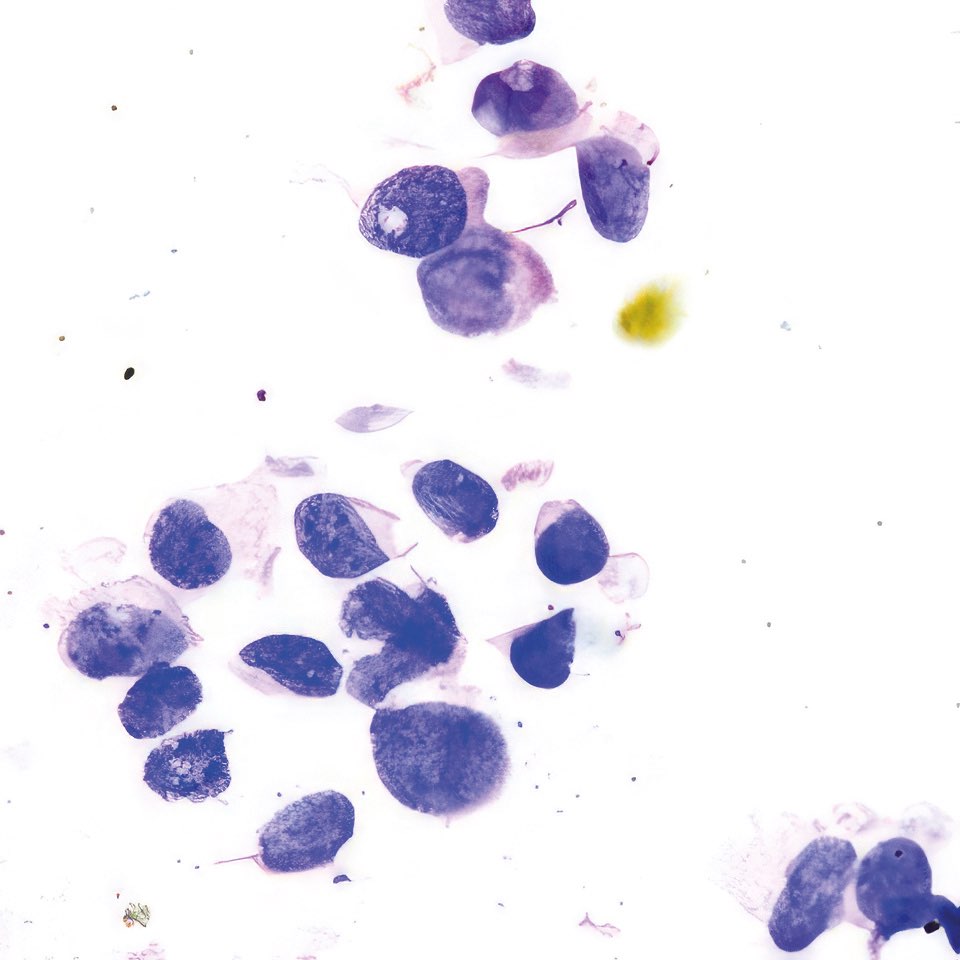

Abbildung 1 – 4: HE-Färbung; 1 – 4, original Obj. 40x, Abb. 4:

zusätzlich vergrößert

Invasive breast carcinoma (IBC NST G3)

Die sich teils überlagernden Zellen erscheinen meist nacktkernig oder haben nur wenig Zytoplasma. Die Kerne variieren deutlich in Form und Größe, sind grob strukturiert und zeigen vereinzelt kleine Chromozentren und Protrusionen. Im Hintergrund etwas Zelldetritus.

Die histologischen Bilder (Abb. 1 und 2) bestätigen die zytologische Diagnose. Weite Teile des Gewebes sind durchsetzt von Tumorzellen, die nur angedeutet Verbände bilden und deutlich polymorphe Kerne aufweisen.

In diesem Fall bestand schon bei der klinischen Untersuchung kein Zweifel an der Karzinomdiagnose wegen eingezogener Brustwarze, oranger Hautfärbung und vergrößertem axillärem Lymphknoten, was klinisch nach WHO-Klassifikation T4bN1 entspricht. Die zytologische Diagnose eines Mammakarzinoms ist nicht immer so einfach. Dies gilt vor allem für das gut differenzierte tubuläre Karzinom, bei dem Größe und Form der Zellen nur schwer von normalen Zellen zu unterscheiden sind 12. Ähnliches gilt für das lobuläre Karzinom, dessen Zellkerne auch nur wenig in Form und Größe variieren; das auffälligste zytologische Merkmal ist die auch im zytologischen Präparat teilweise nachweisbare Indianfile-artige Anordnung 3. Die Trefferquote professionell durchgeführter FNA liegt knapp über 90%. Mag auch die Trefferquote der Dicknadel-Biopsie noch um wenige Prozent höher sein 4, so bietet die FNA besonders in unterversorgten Ländern den Vorteil, dass die Herstellung der Präparate einfacher, billiger und weniger zeitaufwendig ist.